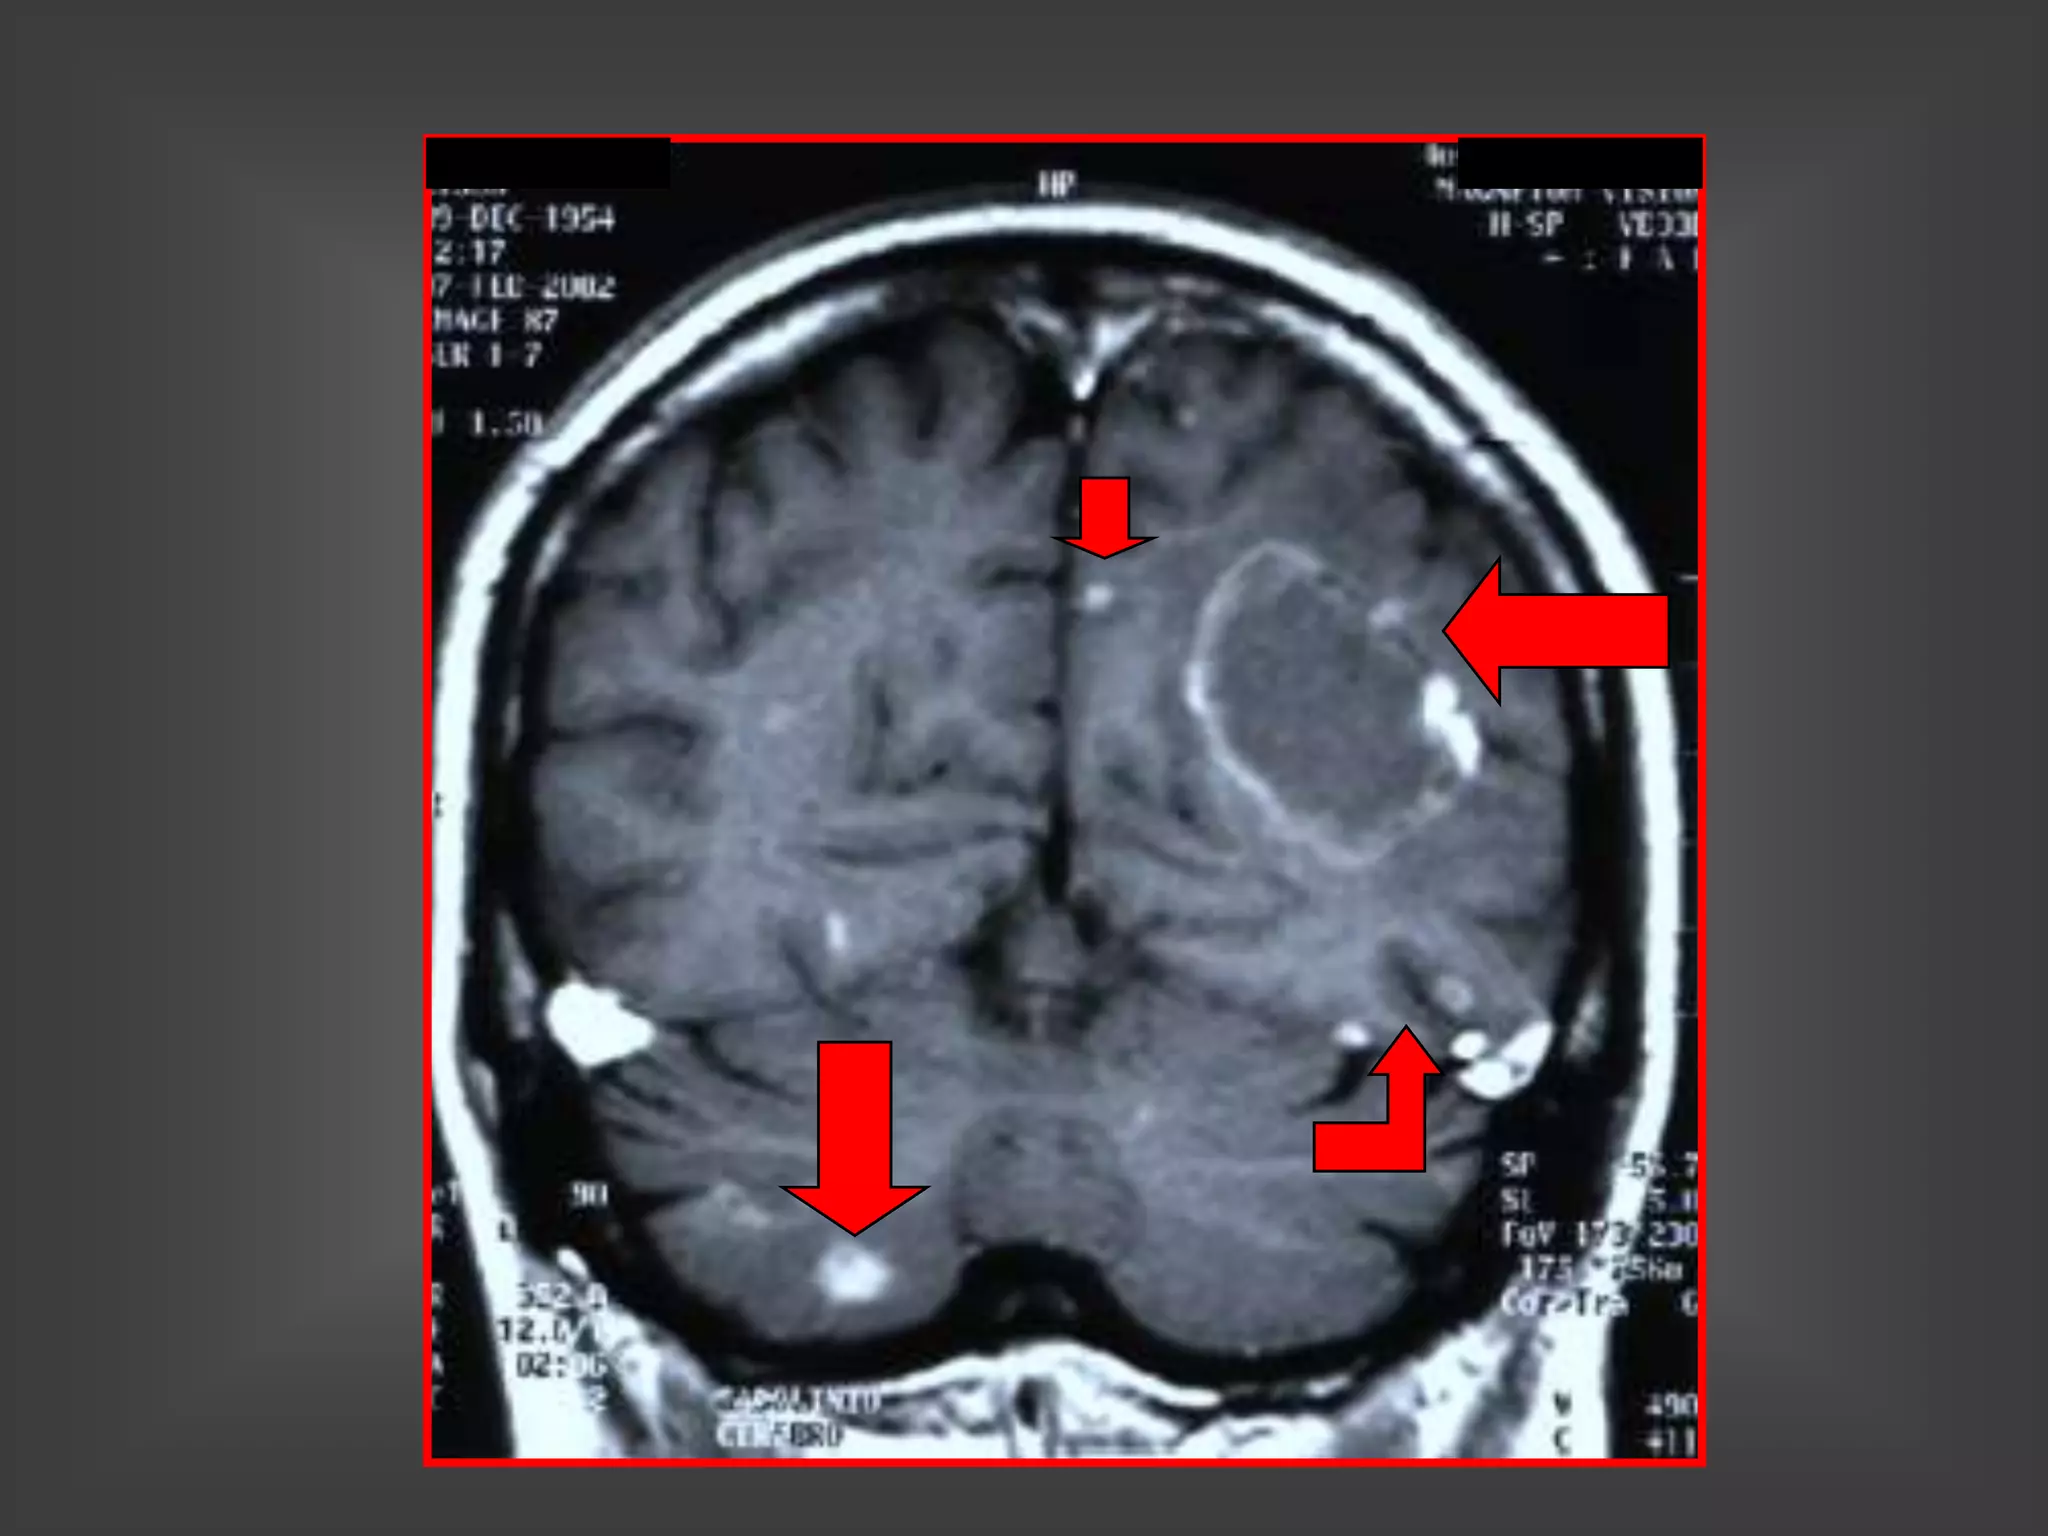

TOXOPLASMOSIS – RNM

LESIONES MÚLTIPLES

TOXOPLASMOSIS LESIONES

MÚLTIPLES EN RNM

TOXOPLASMOSIS

 2 A 3 VECES MÁS FRECUENTE QUE LPSNC

 70 % LESIONES MÚLTIPLES

 UBICACIÓN:

• SUSTANCIA GRIS SUBCORTICAL

• UNIÓN CORTICO/MEDULAR

• TÁLAMO Y GANGLIOS BASALES

 REFUERZO DEL CONTRASTE NODULAR O EN

ANILLO, CON EDEMA Y EFECTO DE MASA